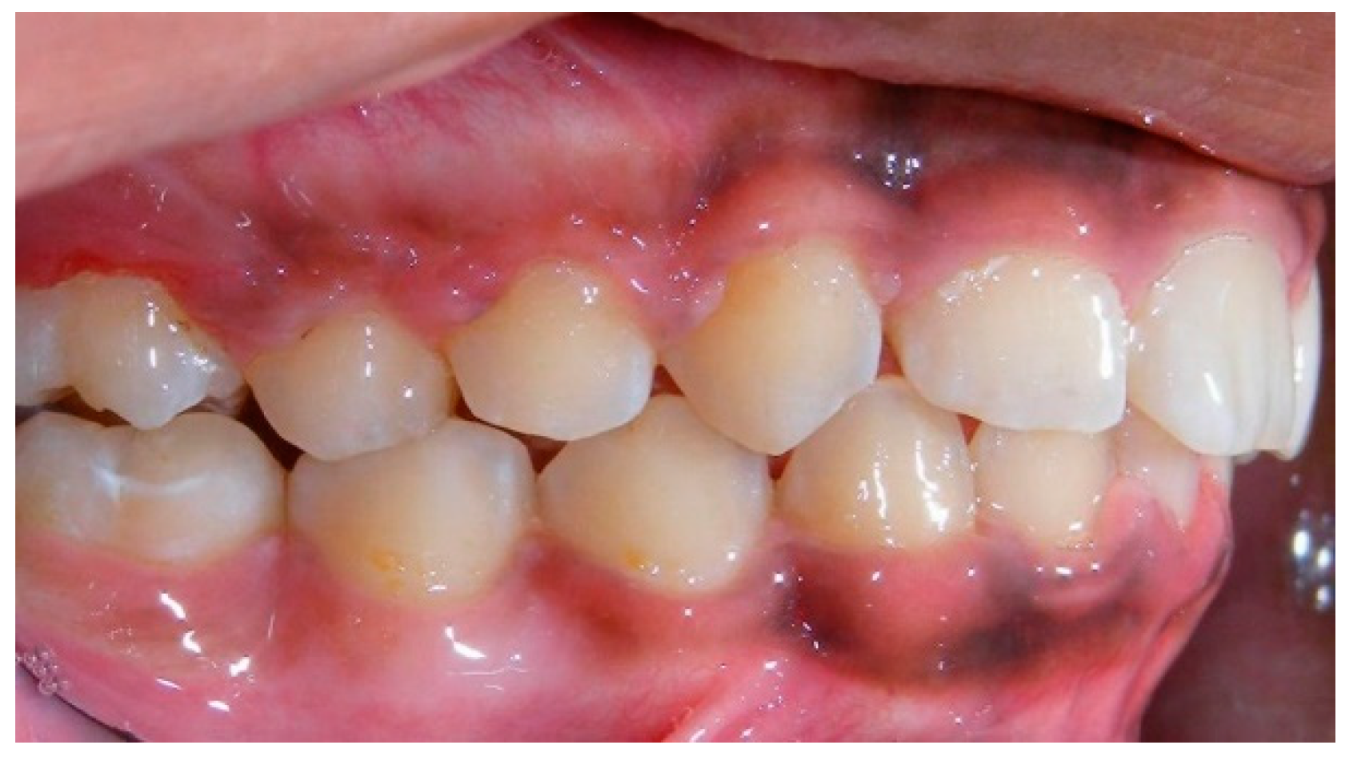

- Evaluation of impacted teeth, a common indication of CBCT in orthodontics. The advantages of CBCT include assessment of the tooth location and position, the stage of development, and status of adjacent teeth. CBCT is justified in these cases, because CBCT has the capability of evaluating the impacted teeth and adjacent structures more accurately than 2D conventional imaging. The benefit–risk ratio is favorable, especially if the CBCT volume is collimated to the impacted tooth. Figure 1, Figure 2, Figure 3 and Figure 4 show an example of impacted maxillary canines, and their proximity to the maxillary lateral incisors. Figure 1 shows an intraoral photograph. The benefit of CBCT acquisition in this case includes the ability to visualize the canines and the lateral incisors in three dimensions, which can be visualized in Figure 2 and Figure 3. In this case, the maxillary right lateral incisor exhibited external root resorption, a finding that would be difficult to see on a conventional 2D panoramic radiograph. Figure 4 shows a Maximum Intensity Projection of a panoramic view derived from the CBCT volume. This unique view is free of magnification, distortion, ghost images, and overlaps frequently seen in conventional 2D panoramic radiography.